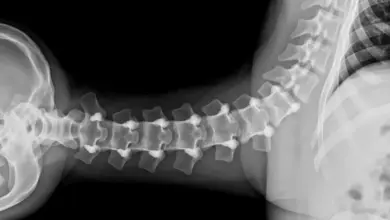

Espondilolistese displásica: causas, sintomas e tratamento

A espondilolistese displásica é um escorregamento congênito entre as vértebras, mais comum em L5 S1. Essa variação surge por malformações…

L5-S1: tudo sobre a articulação lombossacra

A articulação L5-S1 é o ponto de transição entre a coluna lombar e o sacro. Essa região suporta altas cargas,…